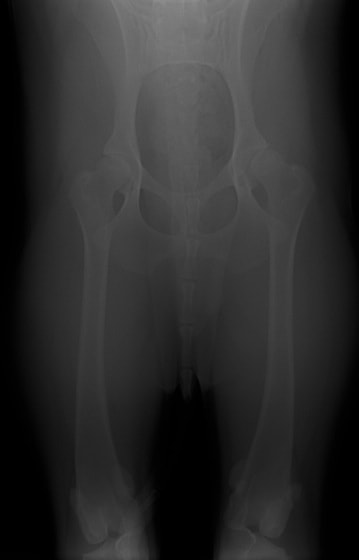

■ 症例24 キャバリア 7か月

左右膝蓋骨内方脱臼(左:グレードⅣ 右:グレードⅢ)

以前から左右後肢の跛行が認められ、整形外科学的検査・レントゲン検査により左右の膝蓋骨脱臼が認められた。症状が重度である左膝の膝蓋骨脱臼整復術を行った。外科手技は縫工筋及び内側広筋の解放、脛骨粗面の外側転位、滑車ブロック形造溝術、内外側関節方の縫縮を実施した。術後一か月時点で、左の膝蓋骨は安定しており経過は良好である。

本症例は成長期における重度の膝蓋骨脱臼であり、術後の再発の可能性もあるため、経過をしっかりと観察していく必要がある。また、今回手術を実施していない右膝に関しても経過を観察し、手術を検討していくこととする。